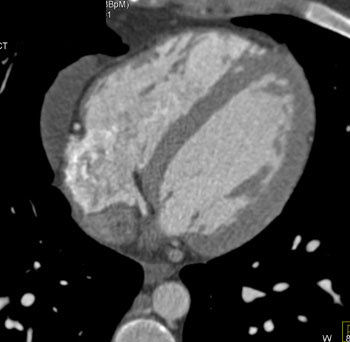

| Diagnosis: Pulmonary Artery Sarcoma

- Rare tumor which arises from the wall of the pulmonary artery

- May look identical (as in this case) to pulmonary embolism. Only hint may be a pulmonary embolism that does respond to appropriate therapy

- Can be in main pulmonary artery or in one of its branches

Pulmonary Artery Sarcoma: CT Findings - Mass may enhance on remain isodense on the CTA of the pulmonary arteries

- Mass may show lobulations with septations

- May fill in entire vessel lumen which is uncommon with pulmonary embolism

- Can range in size from 1-20 cm

Here is a case that was a true saddle pulmonary embolism. Note some of the key differences between the two cases are that the tumor fills in the entire vessel with no wall seen.